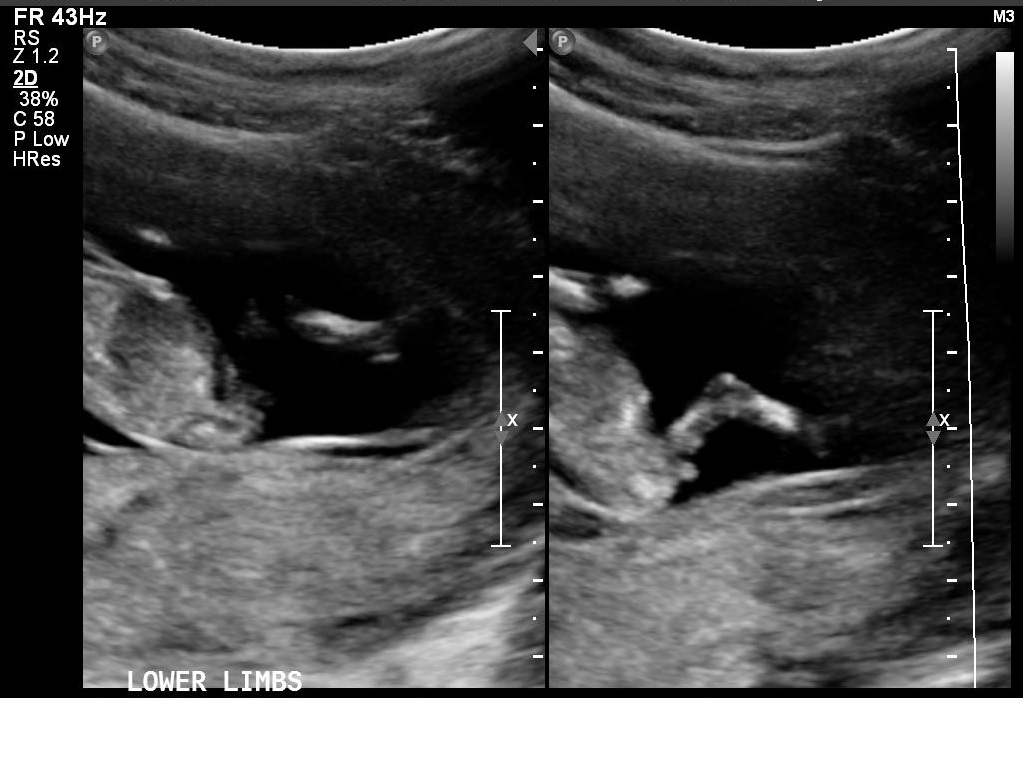

I had my 12w1d ultrasound today, but baby measured ahead at 13 weeks. Bub was very uncooperative and made it hard for the technician to get the NT measurements, which was good in a way because I got to see lots of bub! We got heaps of pictures and I will upload a few here.

I *think* I can tell the gender by the nub pictures but I'd love lots of guesses!!

What do you all think?